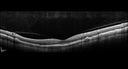

55 year old man: His mother and her siblings have been previously diagnosed with L-ORD - an autosomal dominant dystrophy resulting from a mutation in the c1qtnf5 gene on chromosome 11. The right eye has been abnormal for about the last 1.5 months. When he was trying to read street signs he noticed that his vision was not right. He then covered each eye and noticed that the left eye was normal but the right eye had an area that was blurred with a curve in lines. His right eye with initial vision of 20/32 had a CNVM on FA and responded to monthly Lucentis therapy with restoration of vision to 20/25 after monthly injections. The left eye sees 20/16

Late Onset Retinal Degeneration (L-ORD)699 views55 year old with acute vision loss from a CNVM in the right eye. He responded to Lucentis therapy. His mother and her family has been confirmed genetically to have L-ORD and were part of the early reports.00000